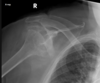

Condroblastoma da escápula